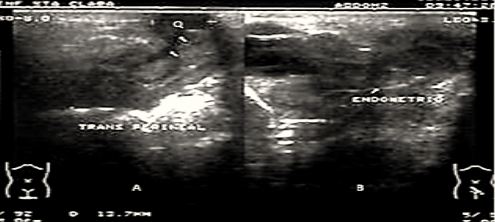

Se realiza ultrasonido transperineal, corroborándose la existencia de imagen ecolúcida, de contornos bien definidos, con presencia de ecos finos en su interior, ubicándose anterior a la vagina, en íntimo contacto con la uretra en su porción más distal (Figura 3).

Fig. 3 Imagen dual de ultrasonido con corte transperineal (A) y suprapúbico (B) con transductor de 8 MZ visualizándose la imagen quística parauretral(Q).